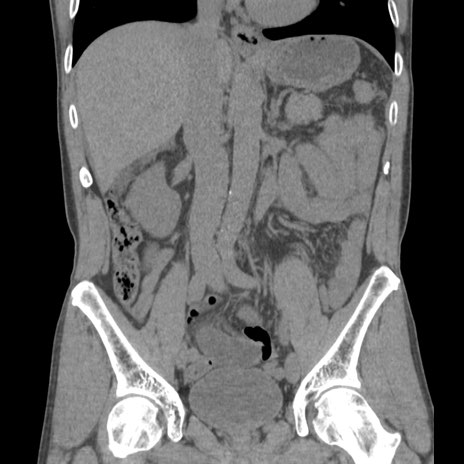

症例56 CT(冠状断像)

横断像